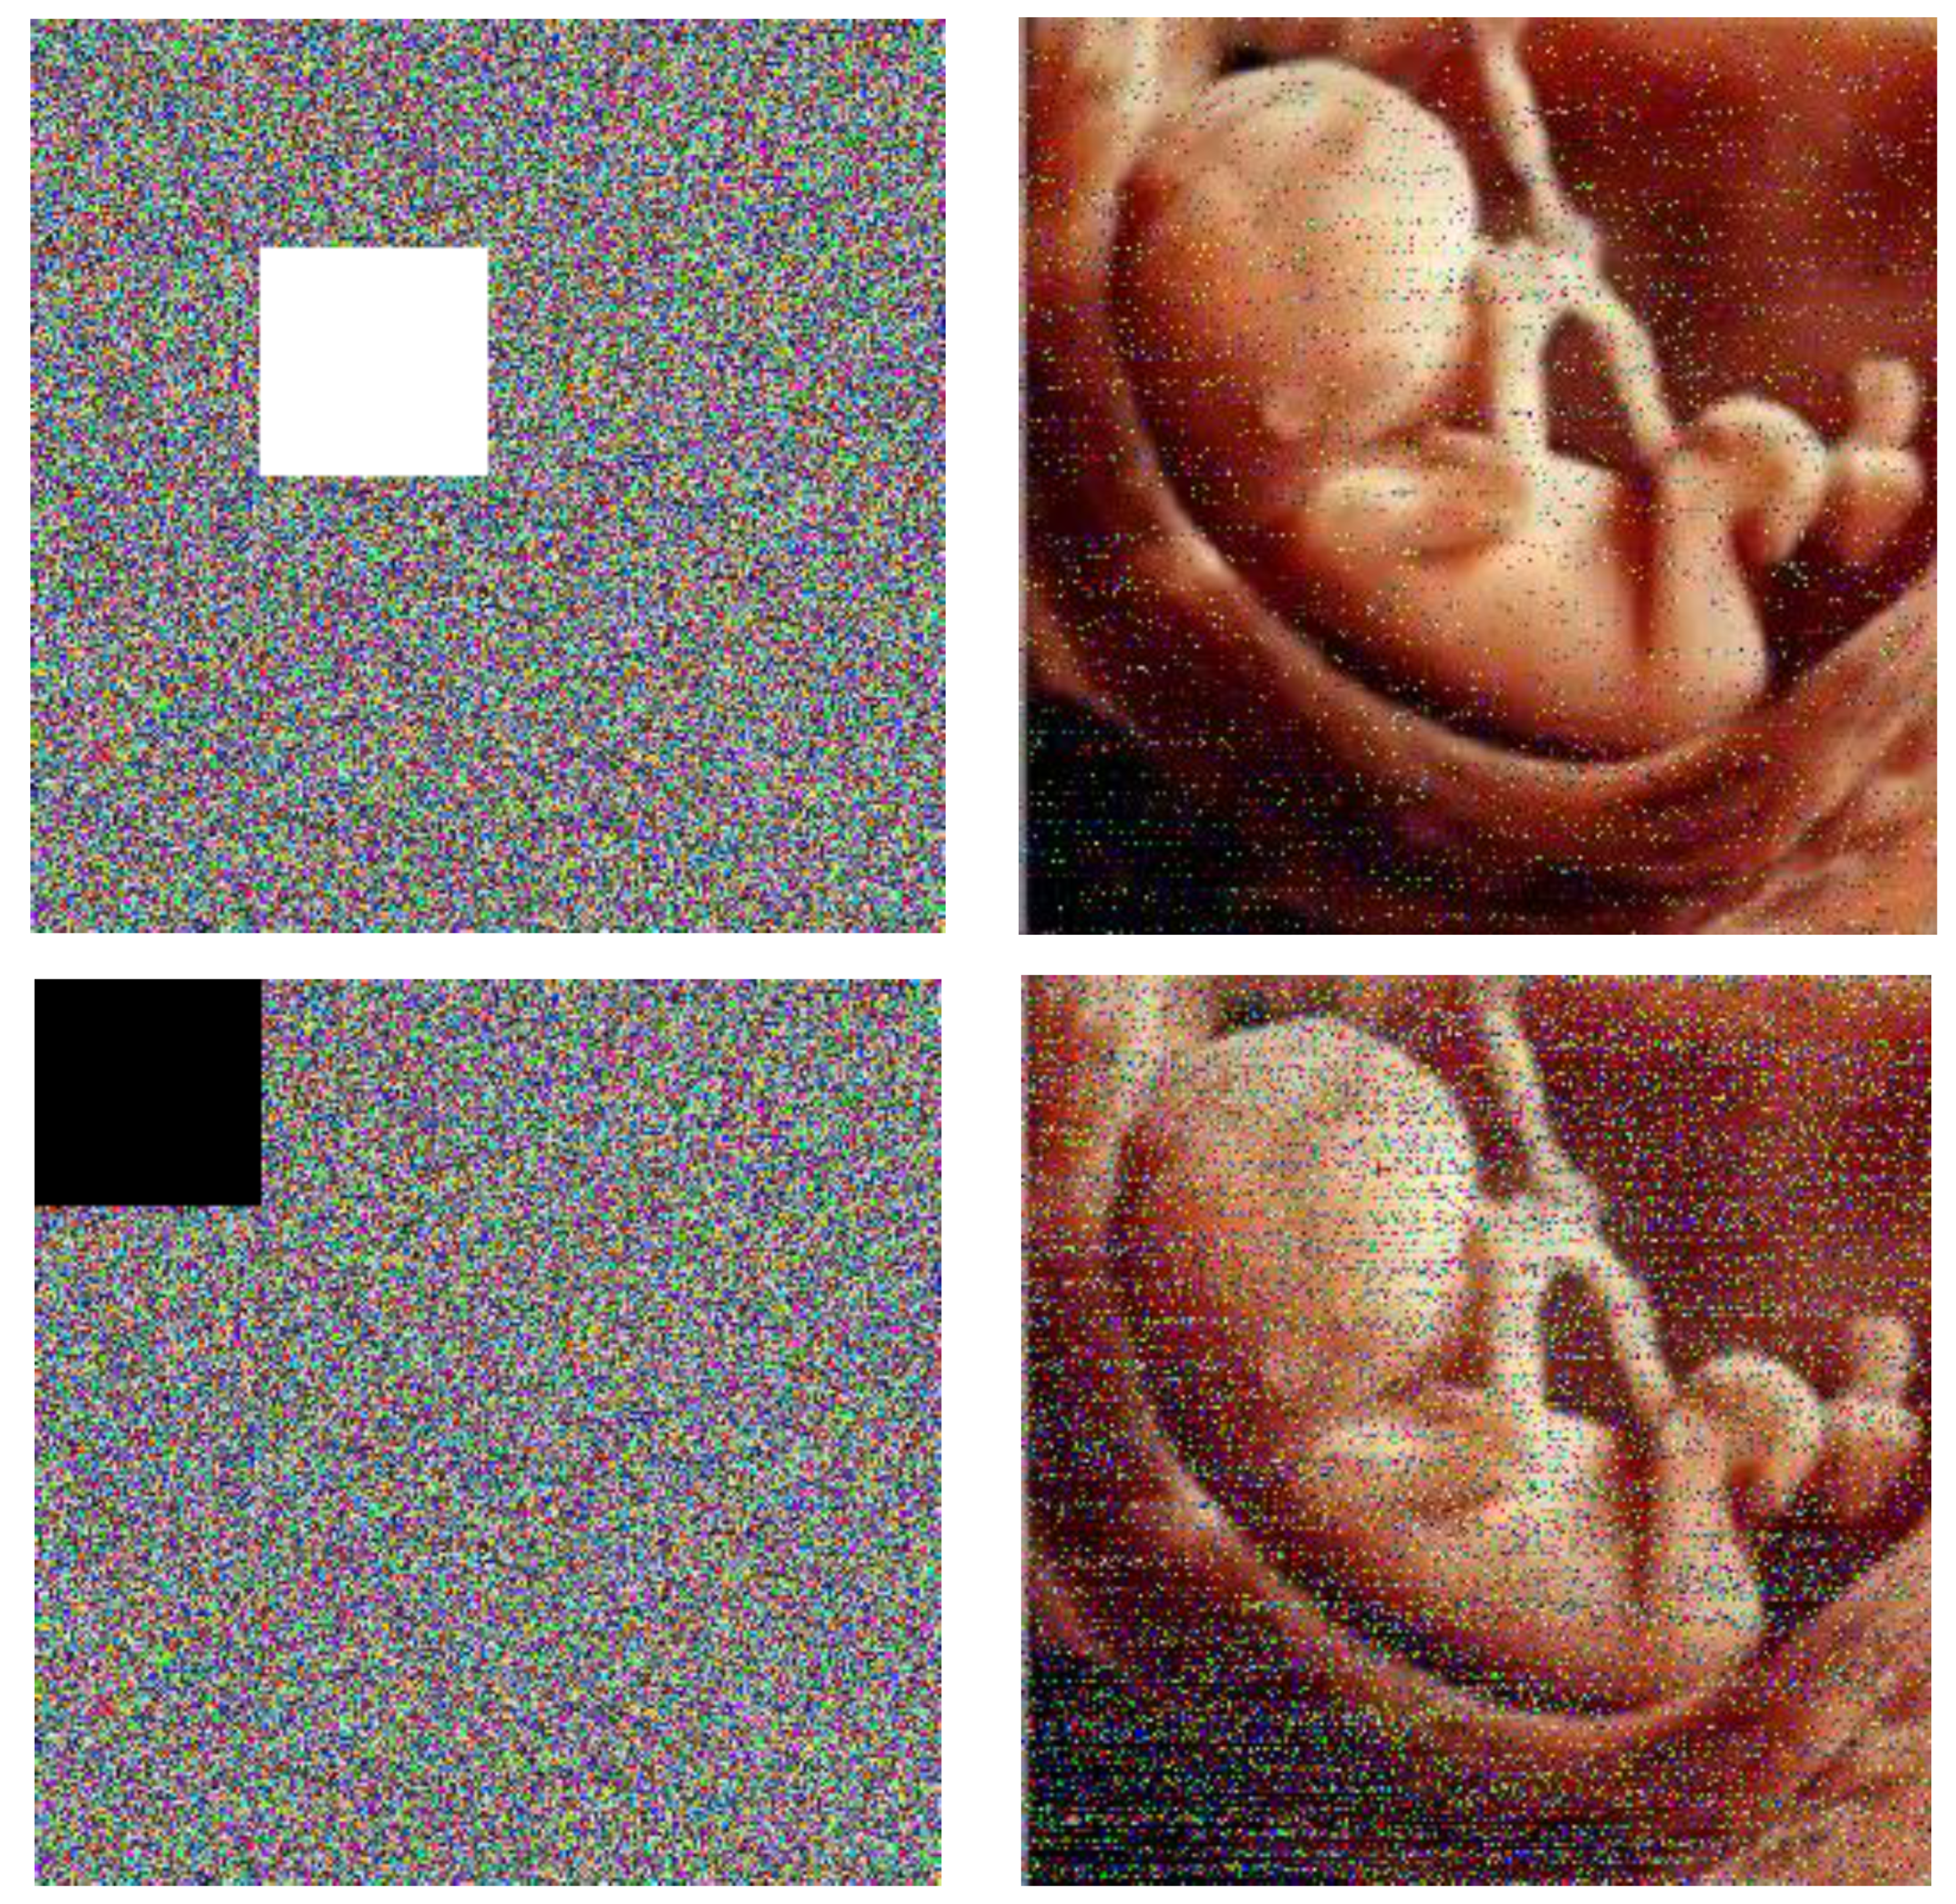

4.9. Noise Attack and Occlusion Attack

In the digital world, the images will unexpectedly experience noise and occlude attacks in the transition process, and an effective cryptology must be strong against them. The baby image is used as the test image. Figure 9 shows the noisy cipher images that are contaminated by Gaussian noise (GN), salt and pepper noise (SPN), and speckle noise (SN) with different noise compression and their decrypted images. As seen from Figure 10, the most information of the plain image can be intuitively identified from the decrypted image’s presentation of the cipher images with different occlusion effects and their corresponding retrieved images. Specifically, the decrypted images still include most date of the baby image. The PSNR (peak signal-to-noise-ratio) is employed to compute the condition of the decrypted image after a possible attack. For a gray image, the PSNR and MSE can be computed as follows:

where MSE shows the mean square error between the cipher image and the plain image , and m and n are the width and height, respectively [25]. The results are explained in Table 7 and Table 8.

Figure 10.

Occlude attack test results.